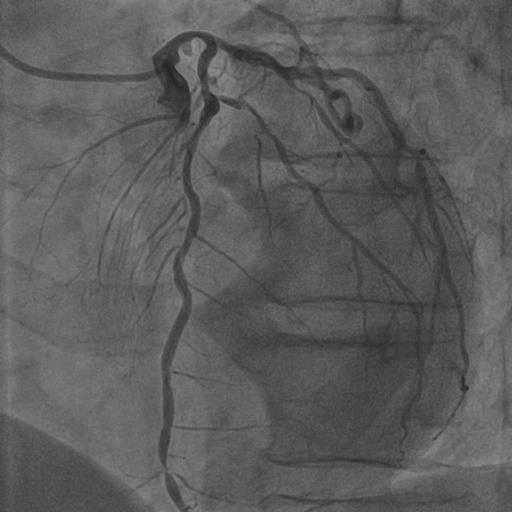

4.1 XACV Dataset

We collect 111 complete records of coronary artery X-ray videos, encompassing the injection, flow through the blood vessels around the heart, and dissipation of the contrast agent. Subsequently, we establish the XACV (X-ray Angiography Coronary Video) dataset. Each video consists of varying numbers of high-resolution coronary artery X-ray images. We invite experienced radiologists to annotate the vascular regions, focusing on one or two frames where the contrast agent is most prominent in each video. The XCAD dataset contains only a single image, and the CADICA video dataset does not provide corresponding ground truth. Therefore, in the following experiments, we conduct all the analyses on our collected XACV dataset and the corresponding GT for each sequence. In Figure 5, we show that compared to other publicly available datasets, XCAD [33] and CADICA [19], our dataset exhibits finer annotations in the vascular regions, providing an advantage for future related tasks. The development and use of our dataset have been approved by our institution’s IRB.